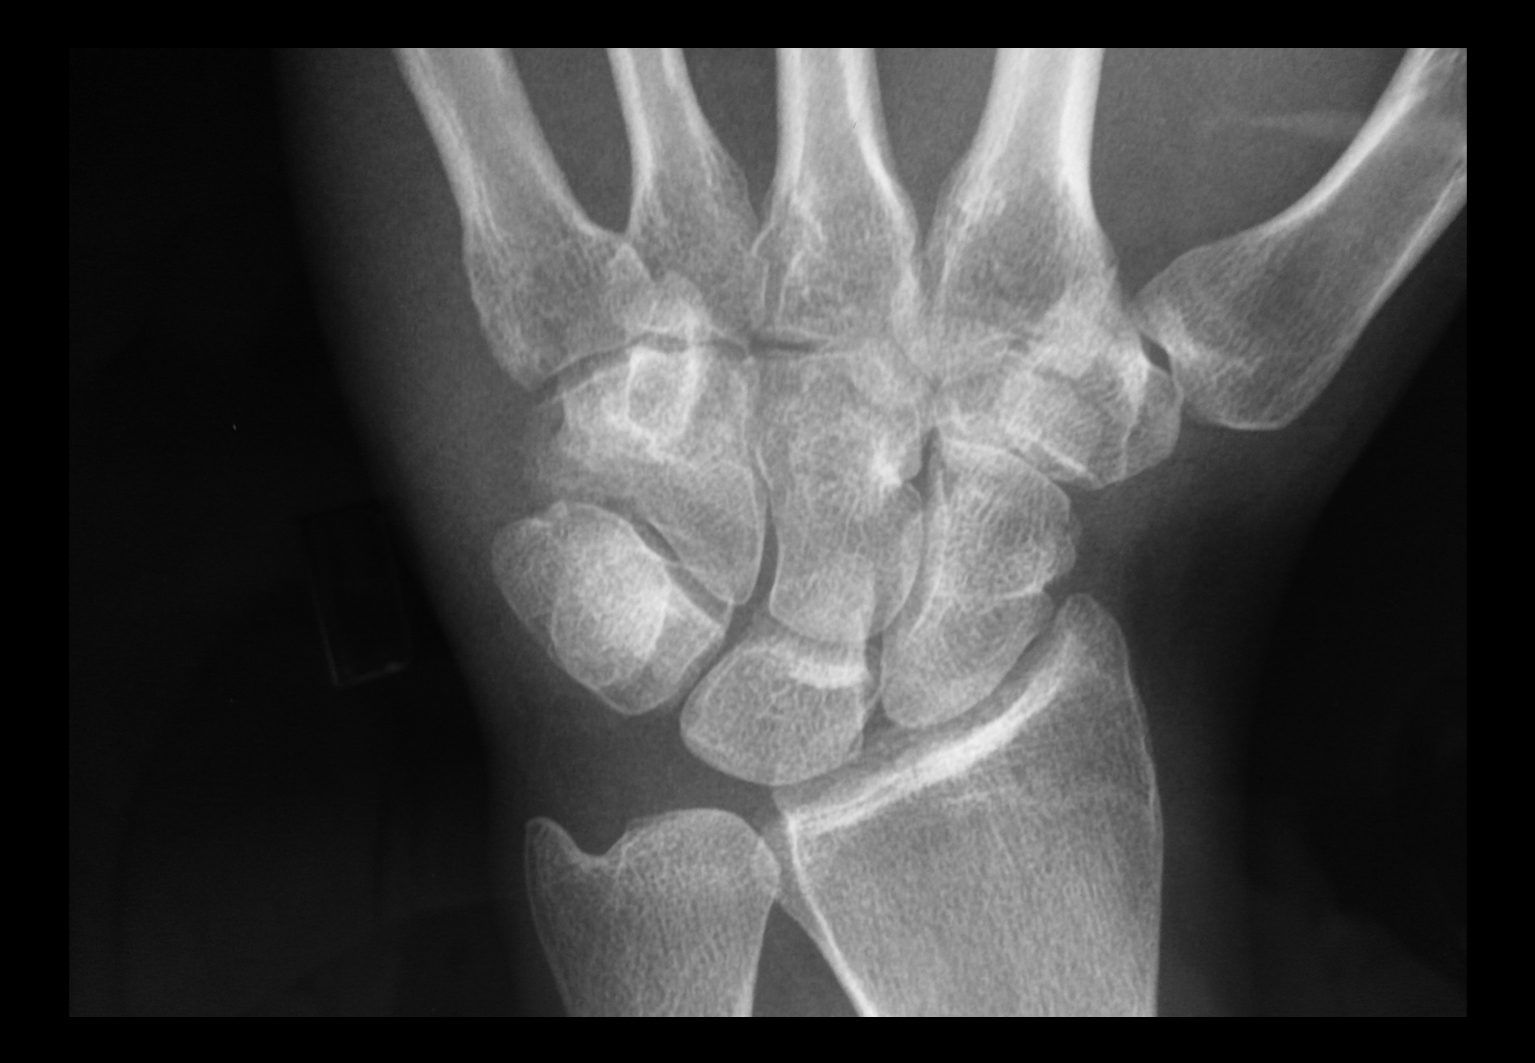

Paciente varón joven con dolor y tumefacción en el dorso de la mano de un año de evolución, refractario al tratamiento médico. Las pruebas complementarias mostraron una tumoración lítica en el hueso ganchoso con características no agresivas. Fue tratado mediante curetaje y relleno con injerto autólogo de cresta ilíaca. El estudio de anatomía patológica diagnosticó que se trataba de un osteoblastoma.

El resultado fue satisfactorio, con desaparición total del dolor e imagen radiológica de restitución completa del defecto óseo, sin signos de recidiva a los 4 años.